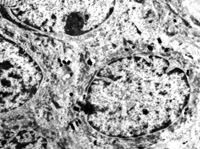

5-2-2 伤后第1天,,,,,,,毛细血管内皮细胞核固缩,,,,,,,管腔内血液凝集和瘀滞  TEM×6000